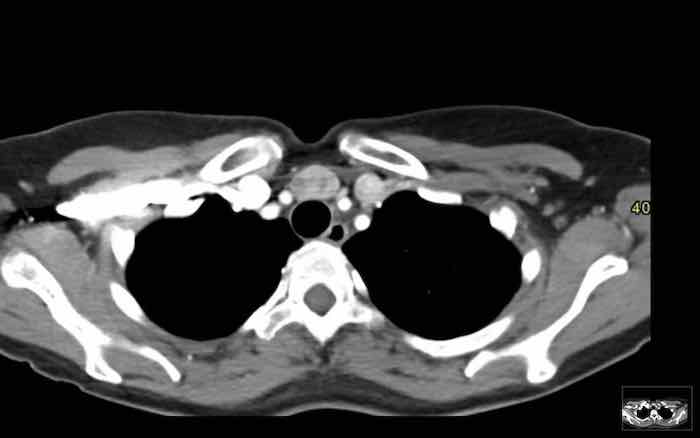

Các hình ảnh này của một phụ nữ 24 tuổi, mắc u xương (osteosarcoma) và được điều trị bằng hóa trị liệu.

Hình ảnh

Tại thời điểm bắt đầu điều trị, tuyến ức có biểu hiện tăng sản.

Tại thời điểm theo dõi 10 tháng, tuyến ức bị teo nhỏ.

Hai năm sau, xuất hiện tăng sản tuyến ức dội ngược.